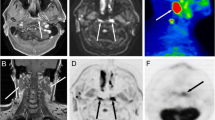

Of those 48 lesions missed by DWI, 20 were malignant (nine tumors [seven recurrent and two primary], nine recurrent lymph nodes, and two metastasis). Fourteen lesions of those 20 (six tumors, six recurrent lymph nodes, and two metastasis) were missed based on technical issues (artifacts). The remaining six malignant lesions (three tumors and three recurrent lymph nodes) did not show restricted diffusion (Fig. 1).

DWI added 20 lesions to the PET/MRI findings, and of those, 11 were inflammatory/reactive lymph nodes and nine were malignant lymph nodes. However, none of these nine malignant lymph nodes changed the overall staging since other lymph nodes defining the N-stage were already detected in PET/MRI without DWI (Fig. 2).

a–c Sixty-nine-year-old man with squamous cell carcinoma of the base of the tongue. a Axial T2w, Axial ceT1w, DWI, ADC, and PET/MRI showing the primary tumor in the base of the tongue. b PET/MRI in different levels showing seven metastatic lymph nodes. c DWI (top) and ADC map (bottom) in different levels showing nine metastatic lymph nodes. In both PET/MRI and DWI, N-staging remains N2c

Concerning the quantitative values of PET and DWI, there was a significant difference (p = 0.001) in SUVmax and SUVmean between malignant and non-malignant lesions (10.5 vs 6.6 and 6.4 vs 4.1, respectively). ADCmean as well as b-valuemean and b-valuemax showed no statistical significant difference between those lesions (Table 6).